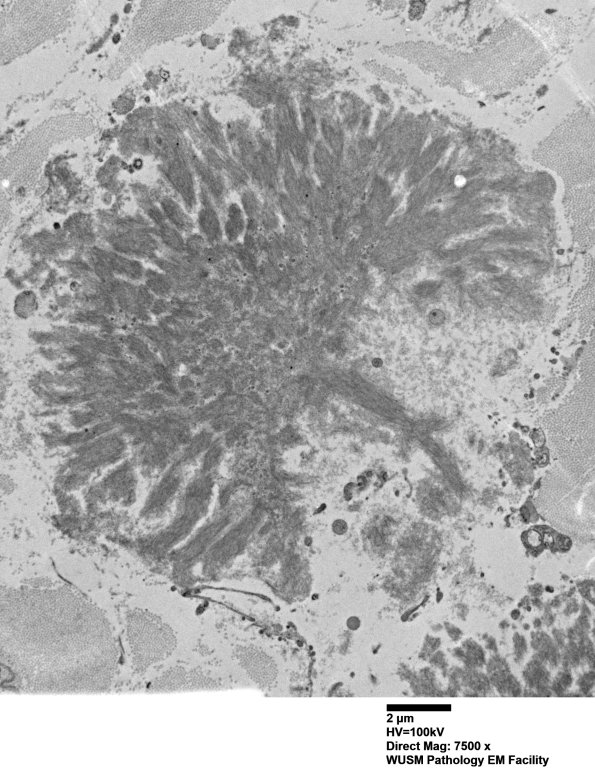

Additional amyloid aggregates seen at multiple magnifications. (electron micrographs)